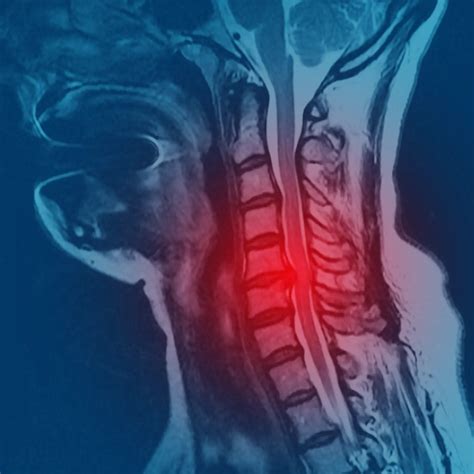

Diagnosing Hernia Discal Lumbar

Diagnosing a Hernia Discal Lumbar typically involves a combination of medical history, physical examination, and diagnostic tests. The diagnostic process may include:

• Imaging tests: Diagnostic imaging, such as X-rays, MRI, or CT scans, can help visualize the spinal discs and identify any herniations or nerve compressions.